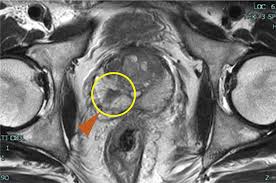

(4) 영상 검사

① MRI, CT, 뼈 스캔 등으로 병기와 전이 여부를 평가합니다.

② 특히 다발성 골 전이가 의심되는 경우 뼈 스캔이 중요합니다.